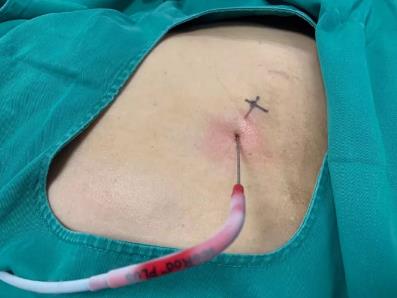

2017年9月29日,從CT影像看到右腎情況更為嚴重。為減緩腫瘤增長的速度,專家進行商議后,最終決定由牛立志教授主刀為安圖叔叔進行了右腎腫瘤冷凍消融術(shù)。手術(shù)開始后,牛立志教授在CT和超聲引導(dǎo)下,同時使用兩根冷凍針固定病灶,精準滅活腫瘤;術(shù)后很成功無不良反應(yīng)。術(shù)后一周進行第二次雙腎腫瘤冷凍消融術(shù)。安圖叔叔兒子笑道:“當時真的很緊張,醫(yī)生勸慰我無須擔(dān)心,都交給他們,我們都很清楚知道父親的病情,真的很感謝也很慶幸我父親遇到復(fù)大的醫(yī)護人員,免受開刀之痛。住院期間醫(yī)護人員很盡心盡力的照顧父親,手術(shù)的成功離不開他們的辛勞付出。”

冷凍治療手術(shù)中